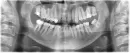

Вернулся в стоматологию, сделали панорамный снимок и обнаружили на нем резорбцию 45 зуба. Пролечили с кальцием под временной пломбой, после чего окончательно запломбировали. Прошло две с половиной недели. Самочувствие все то же, улучшений никаких. Мой стоматолог говорит что если причина лимфоденита и температуры была в 45, то температура должна была уже пройти, а в 47 уверен, что все хорошо. Сказал, что не может мне помочь и что проблема у меня не стоматологического характера. Сам сделал КТ 45, 46, 47 зуба, так как мне кажется, что рентген показывает не все. Очень прошу Вас посмотреть мою КТ. Я уже просто не знаю куда мне идти и что делать.

Резорбция кости присутствует, но тут не в этом совершенно дело. Все три канала не распломбированы до верхушек и то лечение периодонтита, о котором вы говорите, тут совершенно не эффективно. На верхушках обоих корней наблюдаются воспалительные процессы, которые необходимо лечить. Также на 45 зубе наблюдаются изменения. Требуется грамотное эндодонтическое лечение.